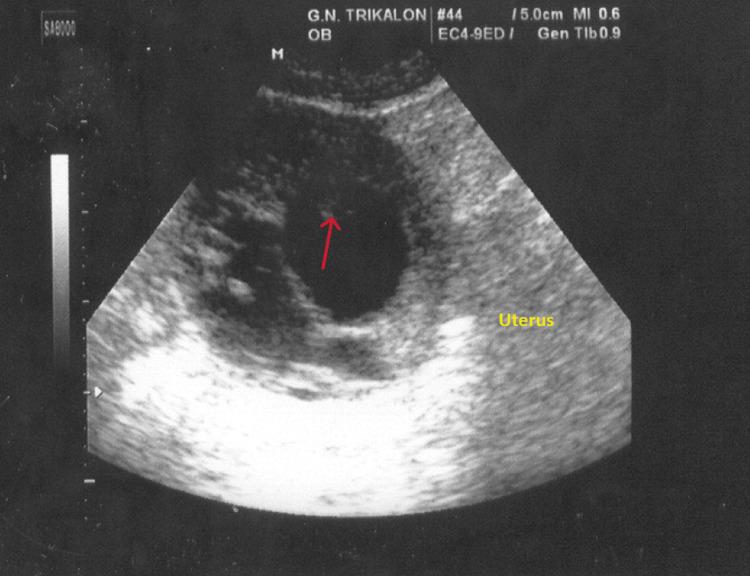

Interstitial ectopic pregnancy is rare (2%-4% of ectopic pregnancies). The atypical clinical presentation of interstitial ectopic pregnancy associated with massive vaginal bleeding is extremely rare and makes early preoperative diagnosis even more difficult. The presentation of our case concerns the early diagnosis and surgical treatment of a patient with an interstitial ectopic pregnancy without rupture, which presented atypically with painless, severe vaginal bleeding. A 27-year-old fourth-term pregnant woman presented with massive painless vaginal bleeding. Secondary amenorrhea was calculated at eight weeks and four days. Transvaginal ultrasound and transvaginal Doppler ultrasound combined with the quantification of beta-chorionic gonadotropin hormone raised the suspicion of interstitial ectopic pregnancy. Intraoperatively, the presence of a large swelling of the right horn of the uterus was established, and a wedge resection was performed with the removal of the corresponding fallopian tube. Three weeks after surgery, the serum beta-chorionic gonadotropin hormone value was zero. In this paper, the rarity of interstitial ectopic pregnancy, the difficulties related to early and correct preoperative diagnosis, and the selection of the appropriate available therapeutic procedures are emphasized, the correct application of which can significantly contribute to reducing the morbidity and mortality of these patients.

摘要

间质部异位妊娠较为罕见(占异位妊娠的2%-4%)。间质部异位妊娠伴有大量阴道出血的非典型临床表现极为罕见,这使得术前早期诊断更加困难。我们病例的呈现涉及一名无间质部异位妊娠破裂患者的早期诊断及手术治疗,该患者表现为无痛性严重阴道出血这一非典型症状。一名27岁的孕晚期妇女出现大量无痛性阴道出血。经计算,继发性闭经为8周零4天。经阴道超声和经阴道多普勒超声检查,结合β-绒毛膜促性腺激素的定量检测,引发了对间质部异位妊娠的怀疑。术中,确定子宫右角有一个大肿块,并进行了楔形切除术,同时切除了相应的输卵管。术后三周,血清β-绒毛膜促性腺激素值为零。本文强调了间质部异位妊娠的罕见性、术前早期正确诊断的困难以及合适可用治疗方法的选择,正确应用这些方法可显著有助于降低这些患者的发病率和死亡率。